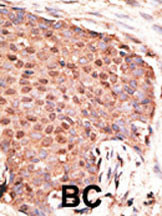

Formalin-fixed and paraffin-embedded human cancer tissue reacted with the primary antibody, which was peroxidase-conjugated to the secondary antibody, followed by AEC staining. This data demonstrates the use of this antibody for immunohistochemistry; clinical relevance has not been evaluated. BC = breast carcinoma; HC = hepatocarcinoma. |